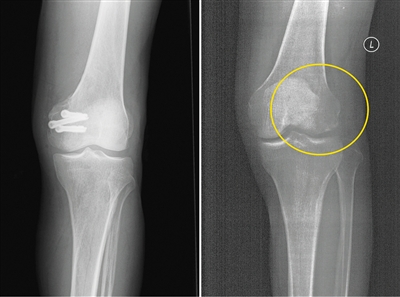

左為使用金屬螺釘后拍攝的影像,右為使用蠶絲螺釘后拍攝的影像。受訪者供圖

在長期的臨床應(yīng)用過程中,金屬材料逐漸顯現(xiàn)出三大缺陷:一是金屬內(nèi)固定往往需要二次手術(shù)取出,大大增加了患者的痛苦及經(jīng)濟(jì)負(fù)擔(dān)。二是金屬的力學(xué)強度遠(yuǎn)遠(yuǎn)超過骨骼,導(dǎo)致應(yīng)力遮擋,影響骨折愈合。此外,使用部分金屬材料術(shù)后無法進(jìn)行CT和磁共振拍攝;即使鈦合金材料可以進(jìn)行檢查,也存在明顯的偽影,螺釘周邊模糊一團(tuán),嚴(yán)重影響影像觀察的效果。

今年5月,患者張強(化名)不慎扭傷,造成左股骨遠(yuǎn)端骨折。由于骨折部位靠近關(guān)節(jié)面,使用金屬螺釘固定時應(yīng)力過大,會影響骨折愈合;1年后還需要手術(shù)將金屬螺釘取出,可能造成二次創(chuàng)傷;颊呷朐褐,團(tuán)隊經(jīng)過詳細(xì)探討病情、細(xì)致閱片后認(rèn)為,該患者符合可降解蠶絲螺釘固定的適應(yīng)證。術(shù)中團(tuán)隊對該患者使用可降解蠶絲螺釘固定骨折塊,術(shù)后的CT片中沒有任何偽影,可以清晰地看到骨折塊已經(jīng)完全復(fù)位,并且解除了患者二次手術(shù)取出螺釘?shù)呢?fù)擔(dān)和困擾。